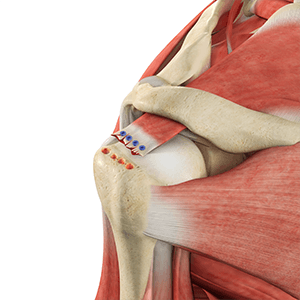

• Revision Rotator Cuff Repair

Rotator cuff repair is a surgery to repair an injured or torn rotator cuff.